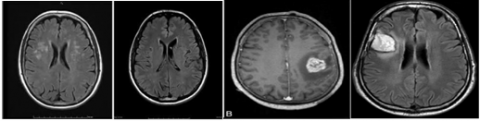

Figure 4 shows few sample images from the kaggle dataset with tumor and without tumor.

Figure 4. Sample images from the dataset without tumor (left 2 images) and with tumor (right 2 images)